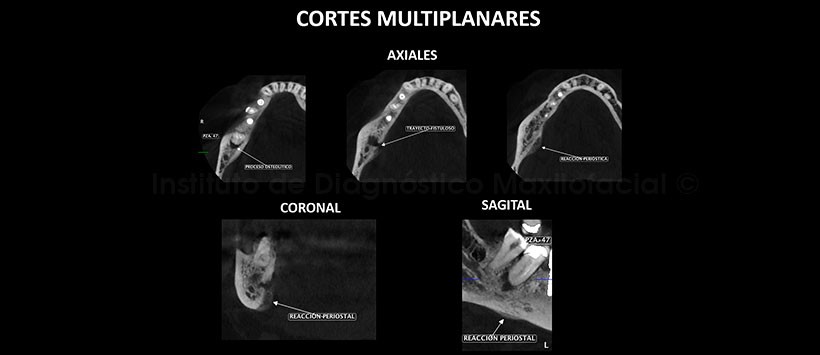

A la evaluación de la tomografía volumétrica (CBCT) mediante cortes axiales, coronales, sagitales (Figura 2) y transaxiales (Figura 3), se encontró una imagen hipodensa periapical de pieza 47 compatible con un proceso osteolítico que generaba un trayecto fistuloso hacia lingual, hiperdensidad ósea difusa circundante que compromete a las corticales del conducto dentario inferior a este nivel y como hallazgo se encontró la presencia de una reacción periostal dependiente de la tabla ósea lingual. Además se encontró como variante anatómica la bifurcación del conducto dentario inferior derecho.